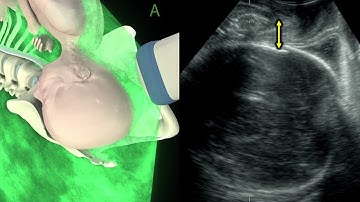

Matlab Projects Automatic Detection of Structures in Fetal Head Ultrasound ClickMyProject